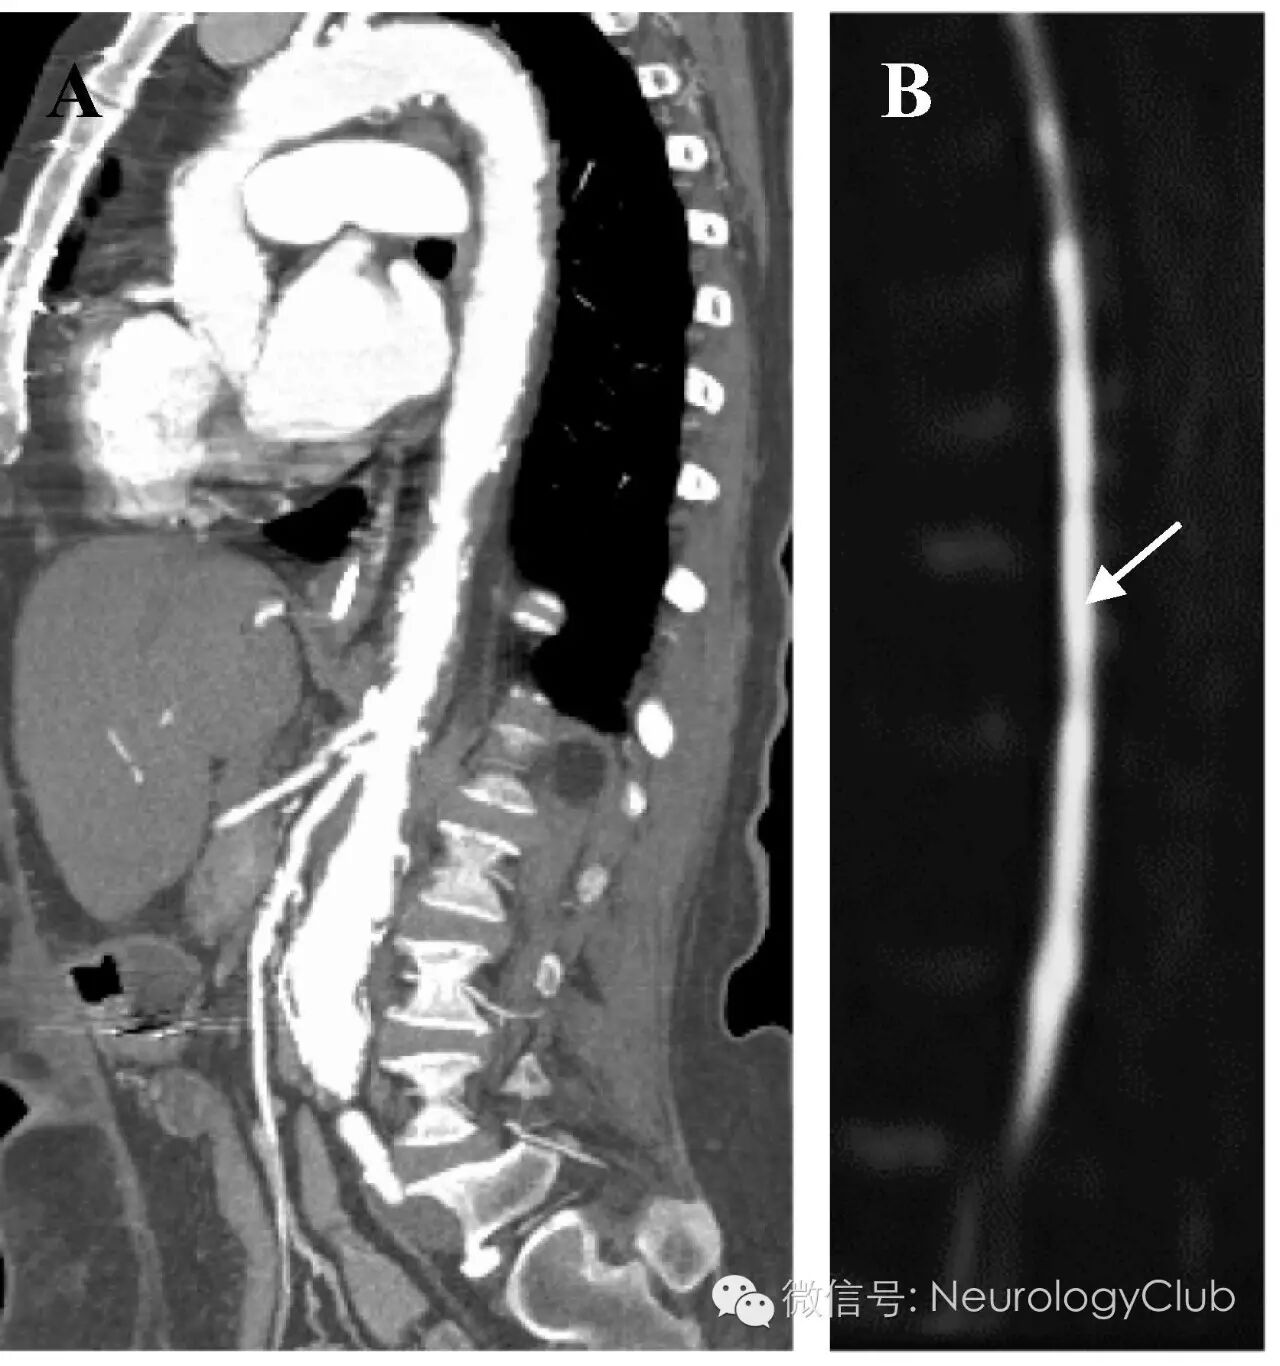

(图2:CT主动脉造影重建[A]和脊髓DWI[B],可见弥漫动脉粥样硬化贯穿主动脉及其主要分支,胸髓和腰髓病灶弥散受限[箭])

脊髓梗死的典型MRI特征为中央T2高信号,不伴有明显的脊髓扩张或强化。如果条件允许的话,DWI上可见对应的弥散受限,与急性脑梗死相同。本例患者的MRI改变明显,横断面T2WI上可见H形高信号病灶(图1A),局限于脊髓灰质,符合对缺氧最敏感的神经元核周体分布区。明显的脊髓弥漫ADC低信号与DWI上高信号区域基本一致,证实病灶弥散受限,提示为急性缺血性过程(图1B-C,图2B)。CT主动脉造影(图2A)证实严重的动脉粥样硬化伴钙化,贯穿主动脉和其主要的腹部分支,这正是该年龄人群脊髓梗死的常见潜在原因。